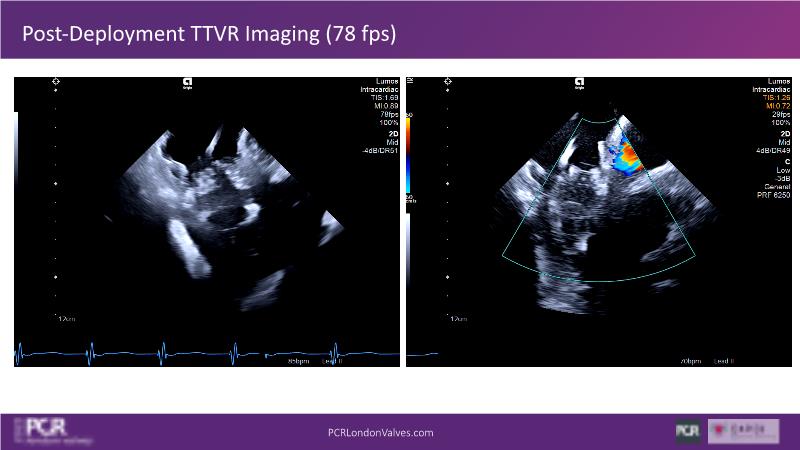

Expert roundtable: 4D ICE in tricuspid interventions

Join this session if you want to get familiar with the 4D ICE technology and the key elements of image guidance for tricuspid interventions, understand how 4D ICE can assist in specific procedural steps during challenging tricuspid interventions, and engage in an interactive discussion with experts about the current use of 4D ICE and insights into future developments.